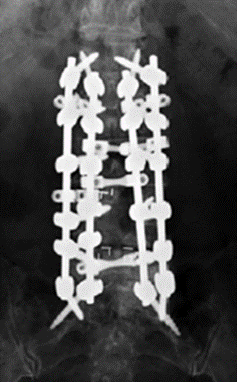

3.降低内固定硬度和减少融合区内固定数量

(1)降低内固定棒的硬度,用钛合金代替钴铬合金棒;

(2)全节段椎弓根螺钉固定改用间隔置钉固定;

(3)适当降低固定融合区内固定强度。

图25 降低内固定硬度和减少融合区内固定数量